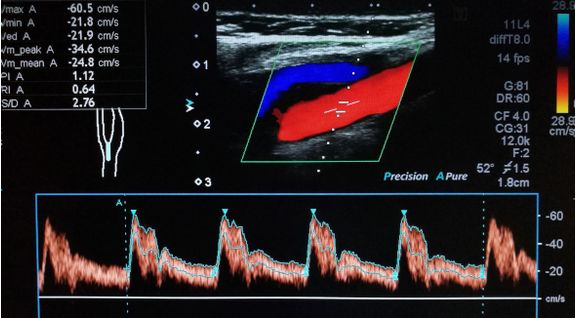

Estado da Arte em Ultrassonografia (Com Mentoria)Especialização Presencial -